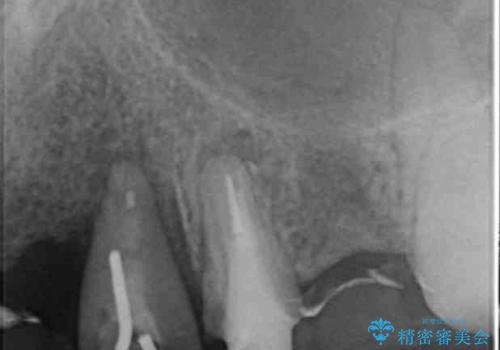

- ブリッジの支台歯であった左上の犬歯が折れたことを主訴に来院された患者様です。

犬歯は歯ぐきの奥深くまで割れており保存不可能な状態でしたが、どうしても抜きたくないとのことでした。

歯を牽引し健全歯質を歯肉縁上まで引き上げ、歯の保存を試みることにしました。